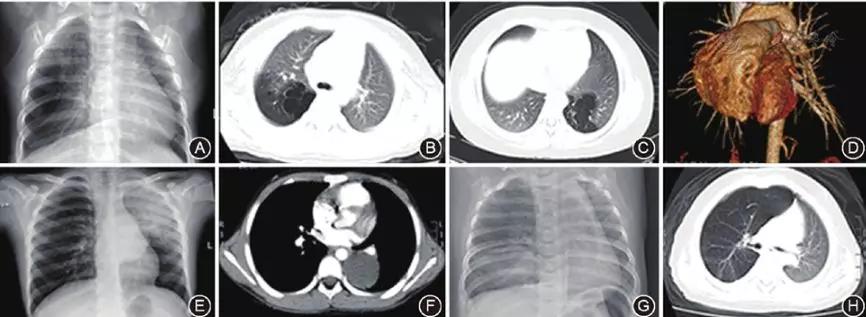

图1 先天性肺囊性疾病患儿手术前胸部影像学图片

A:右肺上叶先天性囊性腺瘤样畸形胸部X线片提示右肺中野外带类圆形囊性透亮影;

B:肺CT显示右肺上叶囊性透亮区;

C:左肺下叶肺隔离症胸部增强CT显示左肺下叶多发囊性透亮区;

D:增强CT血管重建影像;

E:左肺先天性肺囊肿胸部X线片提示左肺中上野片状实变影,左肺门类圆形软组织团块影;

F:增强肺CT显示左侧胸腔片状软组织密度影;

G:右肺上叶先天性大叶性肺气肿胸部X线片提示右肺上野透亮度增高,可见部分右肺组织跨纵隔向左侧胸腔疝入、右肺下野片状高密度影;

H:肺CT提示右肺气肿